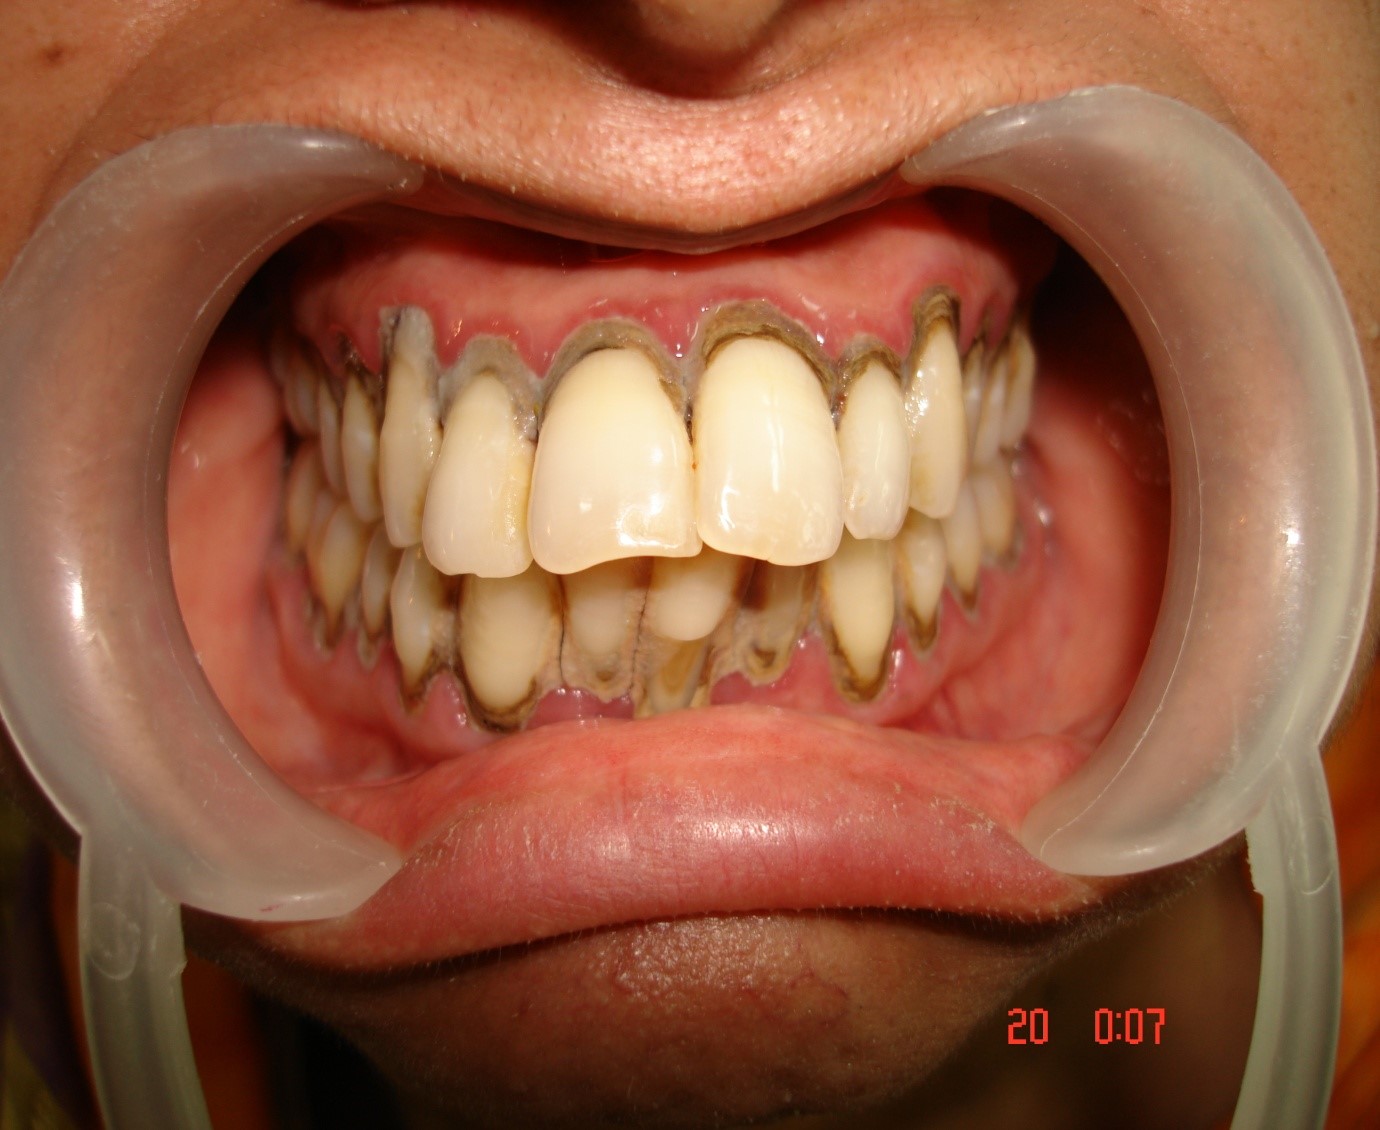

Pyorrhoea is any kind of gum disease in which the ligaments and bone that supports the teeth become inflamed and infected. Bone loss from pyorrhoea is the primary cause of tooth loss in adults. The onset is marked by bleeding of the gums, pus discharge, loosening of teeth. The main aim of the treatment is to control the infection and if possible stop it. The first step is to implement a good oral hygiene program, professional teeth cleaning from your dentist every 6 months. Your dentist may even recommend deep cleaning, gum survey or bone graft depending upon the condition of the teeth and gums.